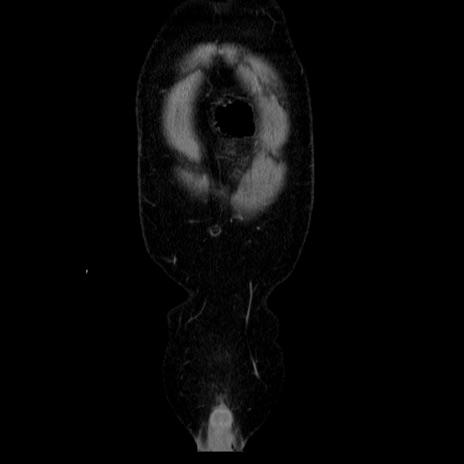

横断像

【症例】40歳代男性

【現病歴】2日前から胃痛あり。徐々に周期的な激痛に変化した。本日になっても激痛があるため受診。

【身体所見】意識清明、BT 38-39℃台あり、腹部:膨満、やや硬、右下腹部に圧痛あり。

【データ】WBC 8500、CRP 23.26